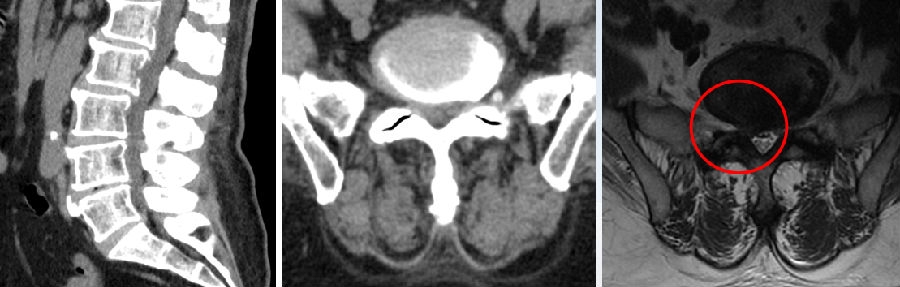

七、术后椎间盘囊肿

病例

男,31岁。

主诉:腰痛伴右下肢疼痛5月,加重2月。

查体:疼痛放射至右侧臀部、大腿外侧、小腿外侧。

思考和建议